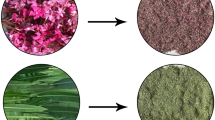

Different plant parts (leaf, stem, fruit) of P. longum were collected from 10 different regions of West Bengal, India (Fig. S2) including both local cultivated and medicinal plant garden. Fresh plant parts were collected and bought to the laboratory. Dr. Avinash Mundhra, Assistant Professor, Department of Botany, Rishi Bankim Chandra College, West Bengal, India, identified the plant specimens. For reference in the future, a voucher specimen (PL01) was stored at the departmental herbarium in the Department of Life Sciences at Presidency University.